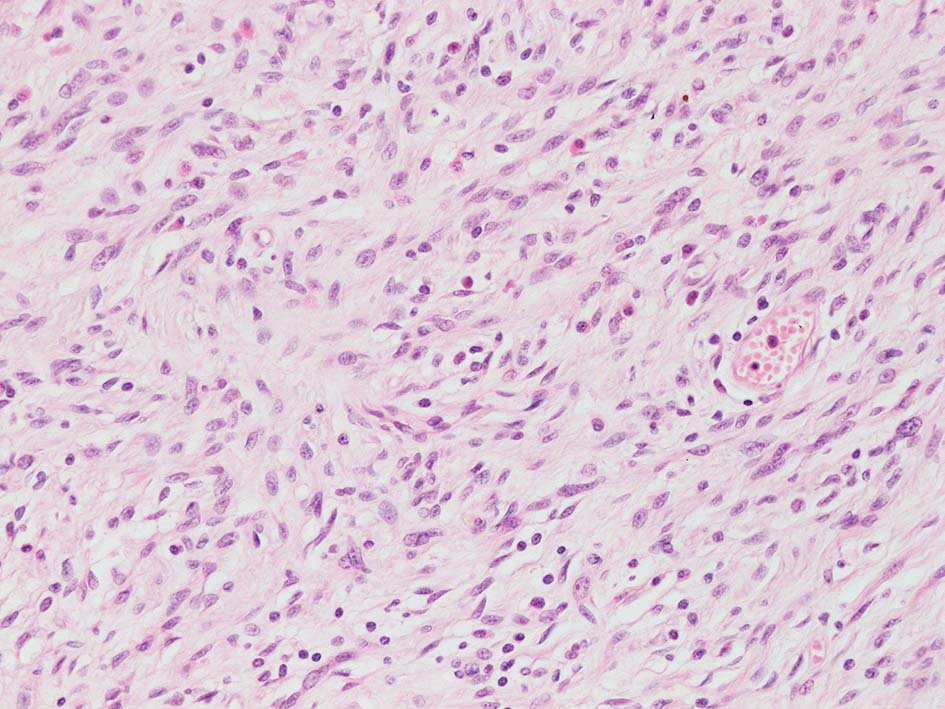

紡錘形異型メラノサイトが著明な間質反応(desmoplasia)を伴い増殖する特殊な色素性病変。*1. desmoplastic neurotropic melanomaは, desmoplastic melanomaのうち神経向性(neurotropism:神経周囲侵襲像)がめだつものでReedら*2が最初に報告した。

いずれも腫瘍細胞の異型性が乏しく, 背景の間質反応がめだつこと, メラニンの存在が目立たないことが特徴である。

“このため両者を臨床的にも病理学的にも色素性病変と診断することが困難”であり, 初回生検時には瘢痕病変や皮膚線維腫などと誤認されることが多い。

病理組織所見*4

リンパ濾胞が細血管周囲に形成され, この部分に異型といえる細胞が増加している(S100+)